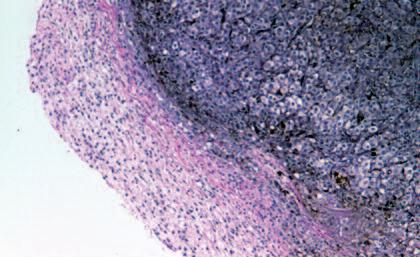

Immagine al microscopio di cellule leucemiche. Le sfere rosse del pacmen rappresentano gli enzimi collagenasi.

Una volta che le cellule tumorali producono enzimi a ‘forbice biologica’ non hanno più barriere e possono invadere e ‘digerire’ lentamente la struttura di ogni organo del corpo.

Questo vale anche per le cellule leucemiche. Una caratteristica di questa forma di tumore del sangue è l’eccesso di produzione di globuli bianchi, i pazienti affetti da leucemia muoiono principalmente, perché queste cellule bloccano la circolazione del sangue. In molti casi i leucemici muoiono per il cedimento di vari organi, in particolare ‘gli organi filtro’: il fegato e la milza. Milioni di globuli bianchi invadono questi organi attraverso il flusso sanguigno. Queste cellule cancerose producono immense quantità di enzimi che digeriscono il collagene, digerendo letteralmente questi organi dall'interno.

La foto nella pagina a fianco mostra una sezione trasversale al microscopio del fegato di un paziente con ‘leucemia linfatica’. Ciascuno dei piccoli puntini viola nella foto è un globulo bianco (in questo caso linfocita) che ha invaso il tessuto del fegato (aree rosa).

Considerando l’enorme quantità di questi puntini viola e il numero di enzimi che assimilano il collagene che ciascuno produce, è facile prevedere l’ingente distruzione del tessuto connettivo e il danno apportato all’organo da questo tipo di cancro.

La leucemia è un buon esempio di come la comprensione dei meccanismi delle cellule tumorali, la produzione di enzimi che digeriscono il collagene da parte dei globuli bianchi, per poter studiare terapie efficaci.

Immagine al microscopio della leucemia linfatica

Globuli bianchi affetti di cancro (linfociti) invadono il fegato L’enorme quantità di collagenasi prodotte da queste cellule distruggono l’organo e causano insufficienza epatica.